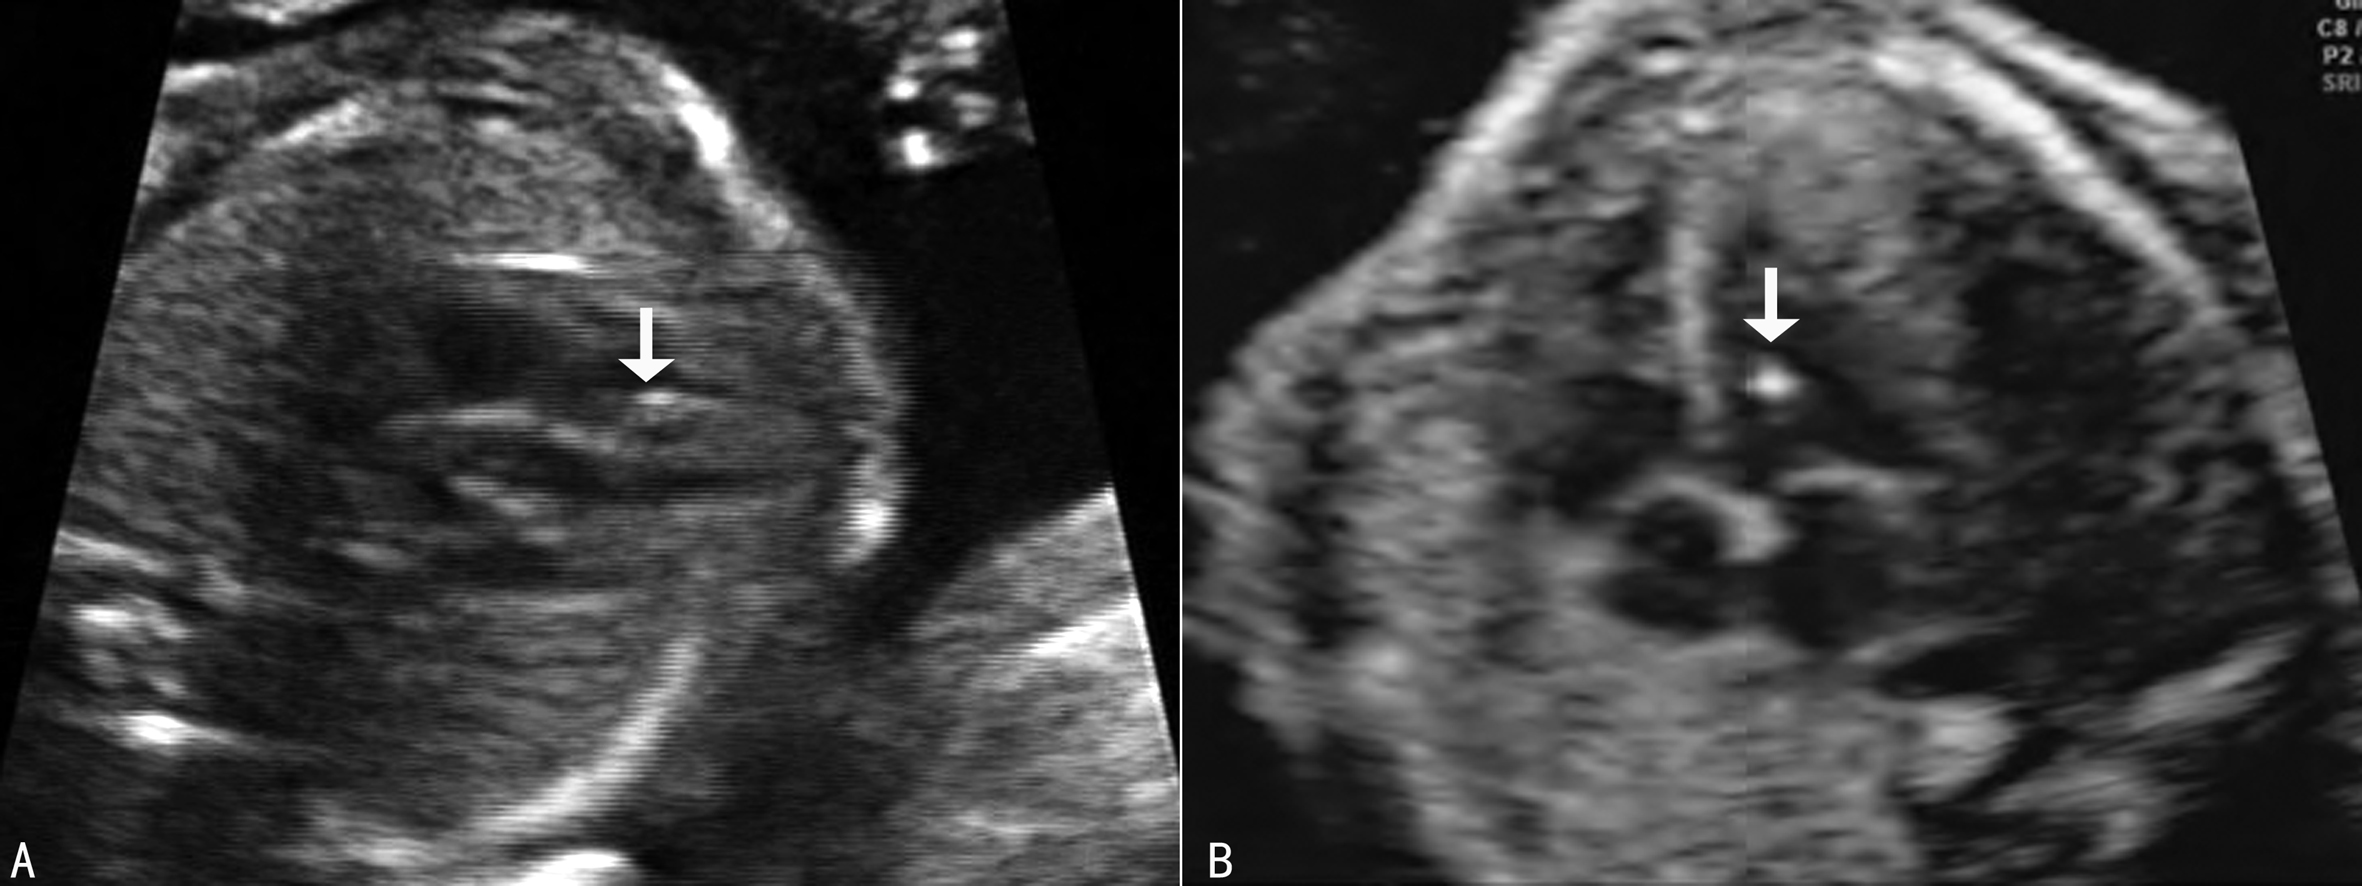

(二)心内强回声灶

心内强回声灶(intracardiac echogenic focus, ICEF)显示为胎儿心脏内的斑点状或索状近似于骨骼强度的强回声灶,长2~7mm,又称为心内钙化灶(图3,图4),多为乳头肌的钙质沉积引起,有人认为可能与炎症或缺氧有关。心内强回声灶可以存在于一个或两个心室内,以左心室内多见,Bettelheim等检查了6995例胎儿心脏,心内强回声灶的发生率为2.15%,其中左心室、左右心室和右心室的发生率分别为96%、4.3%和0.7%,并且在不同的人种中其发生率不同,亚裔人中发生率可能达到30%,而黑人和白人中仅有6%和11%。一般认为,多发性心内强回声灶、范围较大的强回声灶以及累及双侧心室的心内强回声灶胎儿非整倍染色体的危险性增加。Bettelheim等对114例心内强回声灶胎儿进行了核型分析,非整倍体胎儿的发生率为4.39%(5/114)。在综合了多篇报道后Renna等认为心内强回声灶的显示对非整倍体胎儿风险的预测价值在已经使用的各种指标中是比较低的。因此,心内强回声灶的显示仅提示需要仔细的检查以发现有无更多的线索或进一步检查的必要。已经报道合并的染色体异常包括21-三体综合征、13-三体综合征等。

图3 右心室(A)和左心室(B)内强回声灶

图4 A示双心室内强回声灶及B示左心室内两个强回声灶